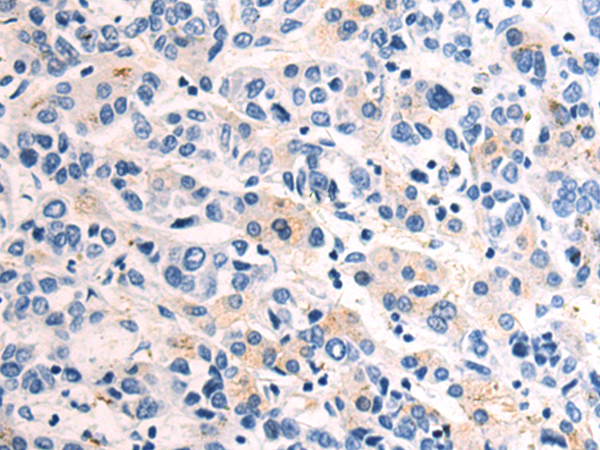

分类: 科研抗体货号: P03997别名: GLUT10, GLUT11, SLC2A11-a, SLC2A11-c应用: IHC反应种属: Human